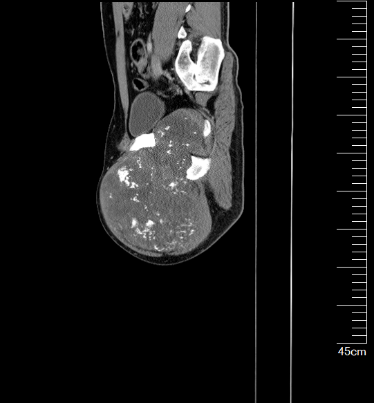

我院骨科王伟东副主任接诊后详细询问了患者疾病发展过程,并为患者做了全身体格检查,仔细查阅了患者的检查报告,综合各方面信息后,诊断患者患有“先天性多发骨软骨瘤病”,并且右耻骨上支的骨软骨瘤已经恶变为继发性软骨肉瘤。目前患者远处脏器尚未出现转移,右耻骨病灶周围解剖屏障尚完整,王主任建议患者手术治疗。

图片 2.png图片 3.png

术前CT